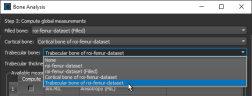

Options for automatically segmenting cortical and trabecular areas, as well as for computing global measurements (see Computing Global Measurements), are available in the Bone Analysis dialog, shown below. Results can be output in comma-separated values files (*.csv extension).

Bone Analysis dialog

- On the Compute global measurements screen of the Bone Analysis dialog, select the region of interest that represents the filled cortical and marrow (trabecular) areas in the Filled bone drop-down menu.

- Select the regions of interest that represent the segmented cortical and trabecular bone in the Cortical bone and Trabecular bone drop-down menus.